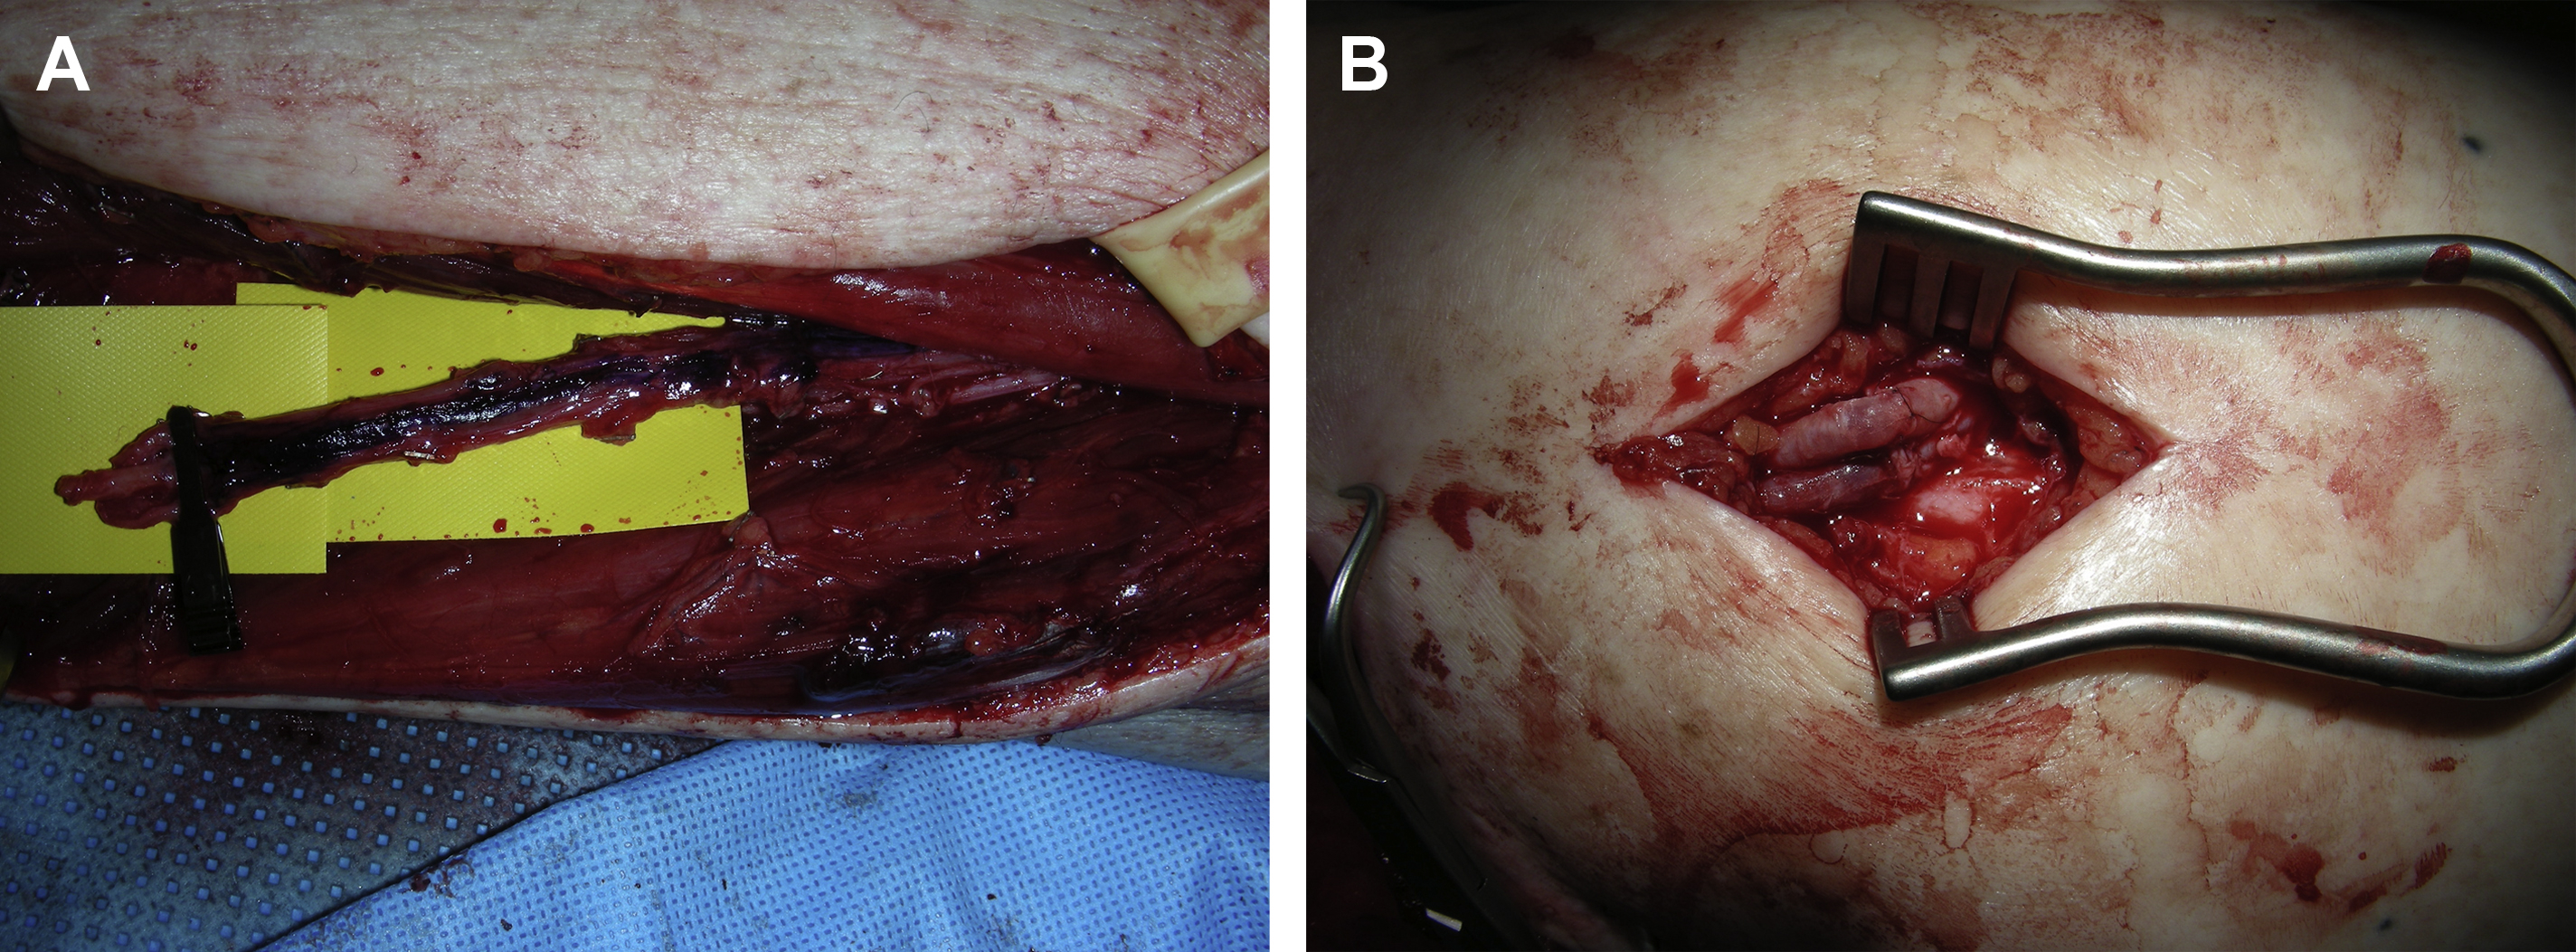

As indicated, the descending branch of the lateral circumflex femoral artery and vein or the anterior tibial artery and vein can be dissected free and used as recipient vessels in a turnover fashion for free tissue transfer to the difficult areas of the lower extremity, such as in the distal thigh or around knee ( Fig. 1 ). In that way, microvascular anastomoses for both artery and vein can be performed without difficulty and vein grafts can be avoided. ,

To ensure a relatively quick and easy flap dissection, the surgeon should know as much as possible about the detailed vascular anatomy of the flap before its dissection. This is particularly true for most perforator flaps. In the author’s practice, a duplex scan is routinely used for the preoperative mapping of the perforators, as well as the pedicle of the perforator flap before the flap dissection. In this way, the size and the number of the perforators that can be selected for the flap, the course of potential intramuscular dissection, and even the depth of the flap’s pedicle are evaluated. With this critical information in mind, a perforator flap, such as an ALT flap, can be elevated smoothly and safely. For an ALT flap dissection, the combination of retrograde and antegrade dissections of the pedicle can be performed for an easy flap dissection once the skin paddle of the flap is elevated ( Fig. 2 ).